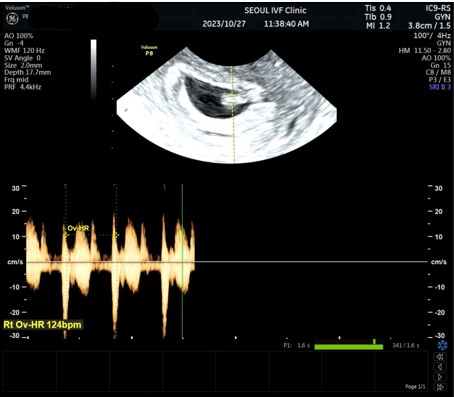

| 가슴 떨리는 임신 이야기를 공유해 주세요. | 결혼후 8개월만에 자연임신이 되어 기뻤습니다. 하지만 기쁨도 잠시 엄청난 복통과 함께 응급실에 가서 자연유산 하였습니다. 그로부터 4년? 후 난임병원에 다니게 되었어요. 한방에 자연임신 성공 후 산과병원으로 옮겼으나 10주에 유산하였고 습유 검사를 받아 혈전 문제가 있음을 알게 되었습니다. 그 후 4번의 인공수정 실패.. 시험관으로 도전하여 1차에 임신 되었으나 더딘 피검 수치로 약물배출 하였습니다. 약물 배출은 내 손으로 넣어야 하는 부담감 때문에 인생이 넘 가혹하다 생각하고 힘들었습니다. 그리고 이번 시험관 2차에 쌍둥이 임신에 성공하였으나 한개의 배아는 도태되어 단태아가 되었습니다. 한아이라도 건강하게 출산하는것이 목표입니다. |

| 치료 도중 느꼈던 가장 기뻤던 순간과 절망적인 것들은 무엇인가요? 잊지 못할 경험이 있나요? | 병원을 옮기지 않고 서울아이비에프에 계속 다닐수 있었던 이유 한가지는 나팔관 조영술 할 때의 기억입니다. 너무 무서워서 덜덜 떨었는데 이경훈 원장님께서 기구를 다 내려놓고 오셔서는 따뜻하게 손 잡아주셨어요. 자기 믿어라 아프지 않게 검사해주신다 하셨습니다. 태어나서 다녀본 병원 중에 의사샘께 이렇게 따뜻함을 느낀 적은 처음이었습니다. |

| 서울IVF여성의원의 난임 치료에 대해 말씀해 주실 것이 있나요? | 다 좋아요. 이경훈선생님과 간호사 선생님들을 믿고 하다보면 끝이 옵니다. |